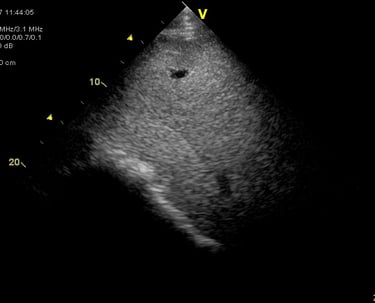

Heeft uw paard een hartruis? Dan is het aanbevolen om een echocardiografie (hartonderzoek) en een inspanningstest met elektrocardiogram (EKG) te laten uitvoeren. Zo kunnen we beoordelen of het veilig is om uw paard te berijden. Een hartruis is namelijk niet altijd een probleem. Met een echocardiografie onderzoeken we of het hart een normale structuur en werking heeft en bepalen we de ernst van eventuele klepafwijkingen.

Voor een uitgebreid hartonderzoek hoeft u niet langer naar een kliniek. Zowel de echocardiografie als de inspanningstest met elektrocardiogram kunnen eenvoudig bij u ter plaatse worden uitgevoerd.

Hartonderzoek - Echocardiografie - Electrocardiografie (EKG)